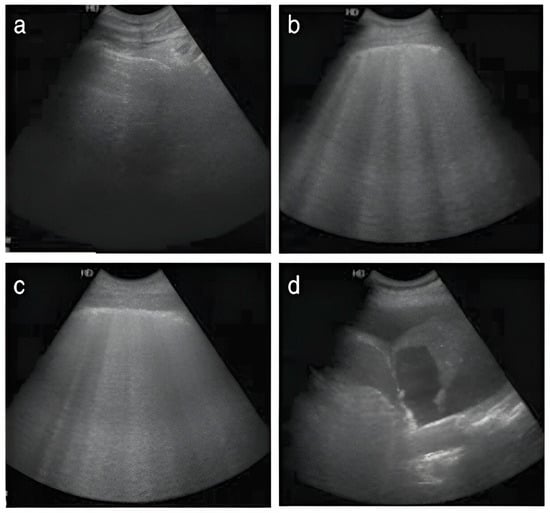

- Volpicelli, G.; Mussa, A.; Garofalo, G.; Cardinale, L.; Casoli, G.; Perotto, F.; Fava, C.; Frascisco, M. Bedside lung ultrasound in the assessment of alveolar-interstitial syndrome. Am. J. Emerg. Med. 2006, 24, 689–696. [Google Scholar] [CrossRef] [PubMed]

- Seibel, A.; Zechner, P.M.; Berghold, A.; Holter, M.; Braß, P.; Michels, G.; Leister, N.; Gemes, G.; Donauer, R.; Giebler, R.M. B-Lines for the assessment of extravascular lung water: Just focused or semi-quantitative? Acta Anaesthesiol. Scand. 2020, 64, 953–960. [Google Scholar] [CrossRef] [PubMed]

- Zhao, Z.; Jiang, L.; Xi, X.; Jiang, Q.; Zhu, B.; Wang, M.; Xing, J.; Zhang, D. Prognostic value of extravascular lung water assessed with lung ultrasound score by chest sonography in patients with acute respiratory distress syndrome. BMC Pulm. Med. 2015, 15, 98. [Google Scholar] [CrossRef] [PubMed]

- Chiumello, D.; Mongodi, S.; Algieri, I.; Vergani, G.L.; Orlando, A.; Via, G.; Crimella, F.; Cressoni, M.; Mojoli, F. Assessment of lung aeration and recruitment by CT scan and ultrasound in acute respiratory distress syndrome patients*. Crit. Care Med. 2018, 46, 1761–1768. [Google Scholar] [CrossRef]

- Lichtenstein, D.A. Lung ultrasound in the critically ill. Ann. Intensive Care 2014, 4, 1. [Google Scholar] [CrossRef]

- Volpicelli, G.; Skurzak, S.; Boero, E.; Carpinteri, G.; Tengattini, M.; Stefanone, V.; Luberto, L.; Anile, A.; Cerutti, E.; Radeschi, G. Lung ultrasound predicts well extravascular lung water but is of limited usefulness in the prediction of wedge pressure. Anesthesiology 2014, 121, 320–327. [Google Scholar] [CrossRef]